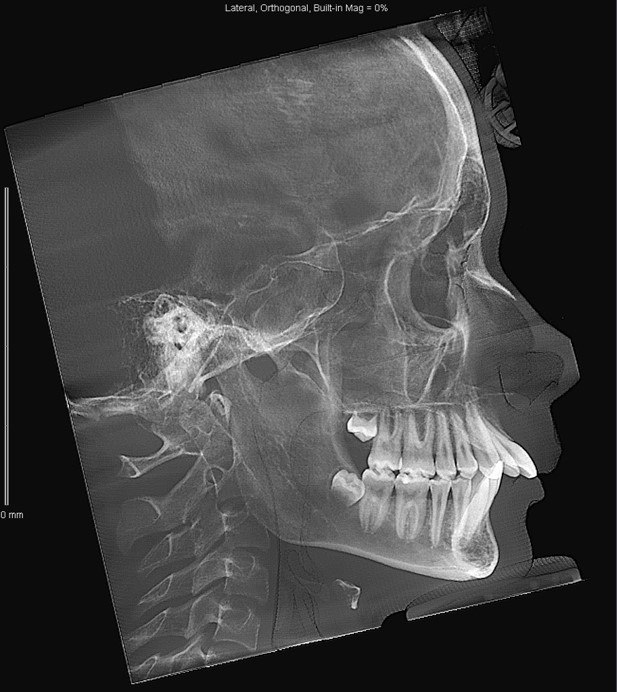

«Подросток 15 лет обратился с жалобой эстетического характера, – рассказывает ортодонт. – Зубы очень сильно выпирали вперёд. Надо было тщательно собрать анамнез, проанализировать гипсовые слепки, фото и рентгеновские снимки, чтобы выбрать оптимальный метод лечения».

Вместе с пациентом Анастасия Борисова начала большую работу с использованием брекет-системы и микроимплантов. И подросток, и его родители были готовы к длительному лечению.

«Поэтому все мы очень обрадовались, когда удалось добиться результата всего за 12 месяцев, – делится доктор. – Если бы пациент затянул с обращением к специалисту, то без операции на челюсти уже нельзя было бы обойтись».